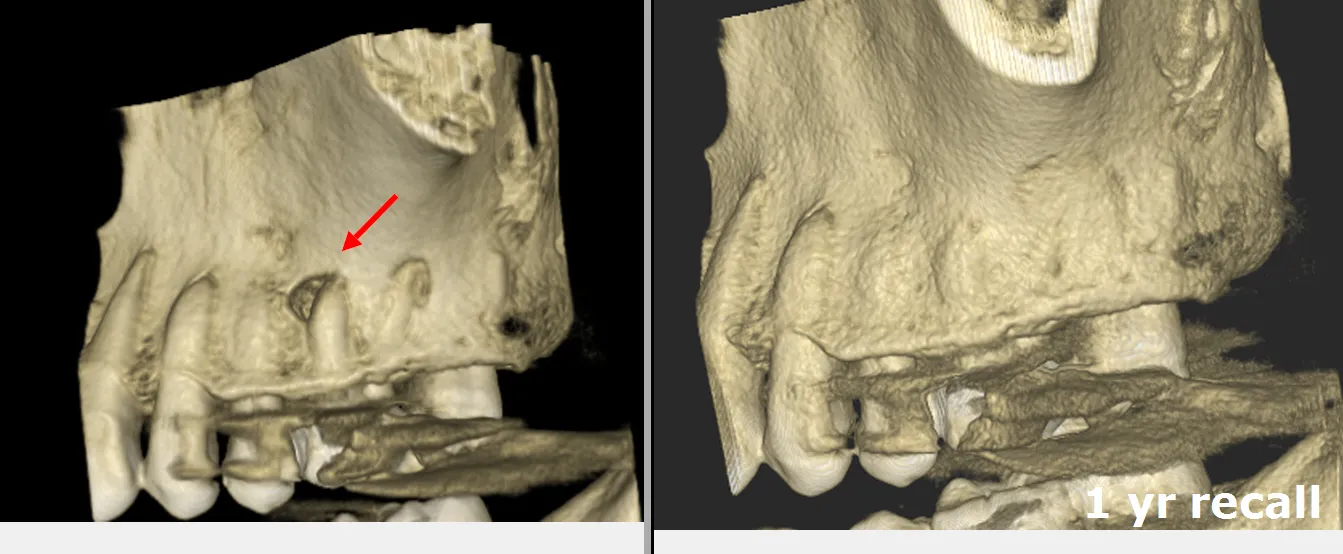

- Diagnosis: The process of diagnosis starts with a thorough examination of the teeth and gums by the dentist. X-rays may be taken to check the inside of the tooth and surrounding bone. Sometimes a 3D Cone beam CBCT scan may be necessary.